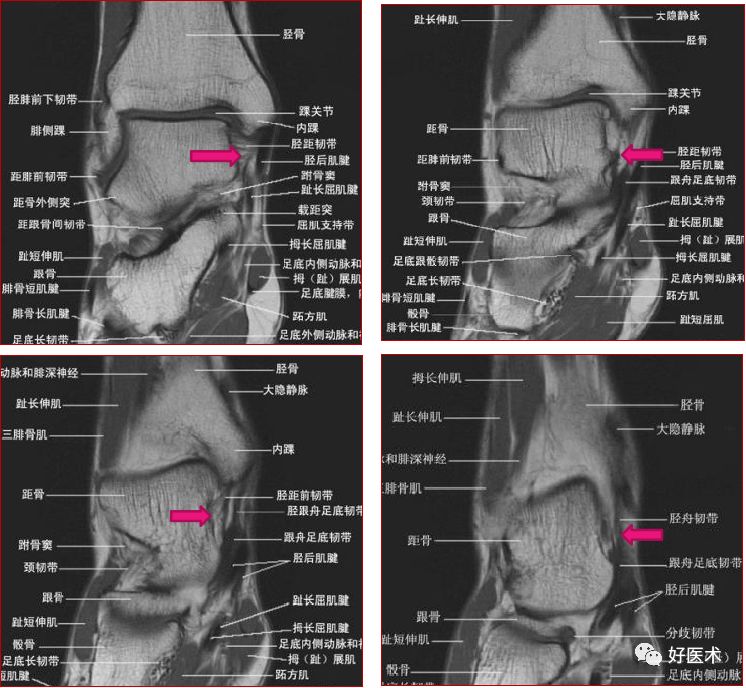

一、解剖和扫描方法

扫描定位